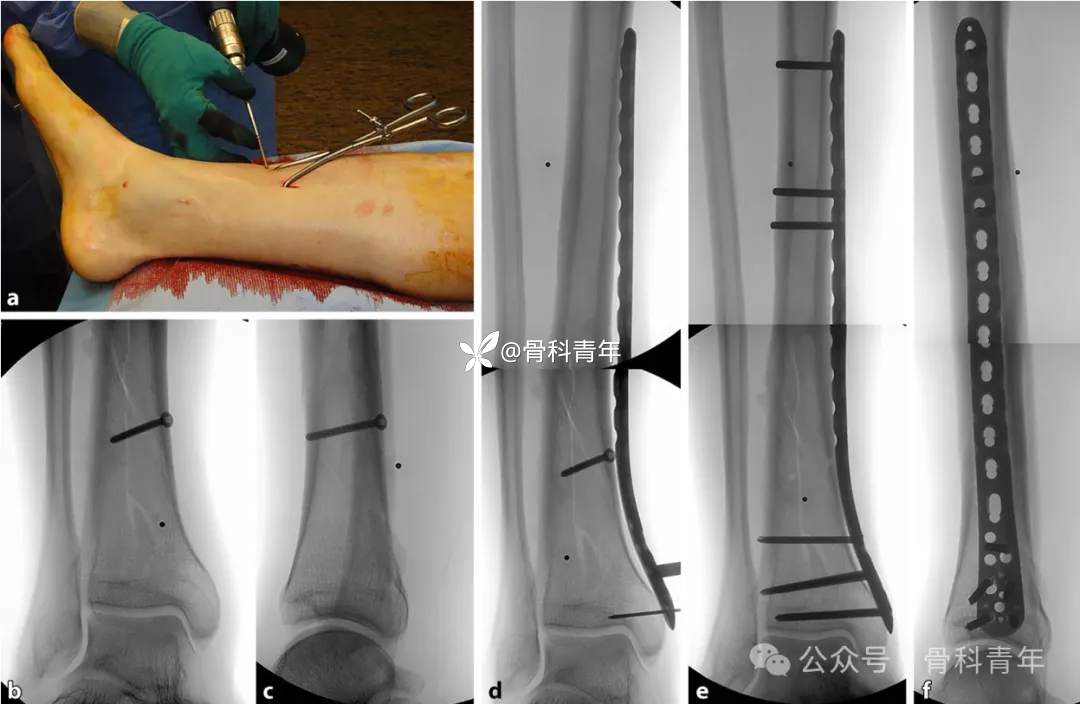

对胫腓骨干简单长斜形或螺旋形骨折,手术追求解剖复位,骨折线完全匹配。在可闭合情况下,优先选择复位钳钳夹复位。有医生为节约手术时间,直接切开复位,可能对骨折愈合产生不利影响。

经复位钳钳夹复位后,透视复位满意,可经骨折线置入全螺纹螺钉稳定骨折断端,可常规插入钢板固定骨折: